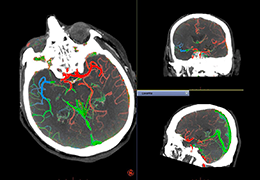

ANYTHINK 经导管主动脉瓣膜置换术分析系统